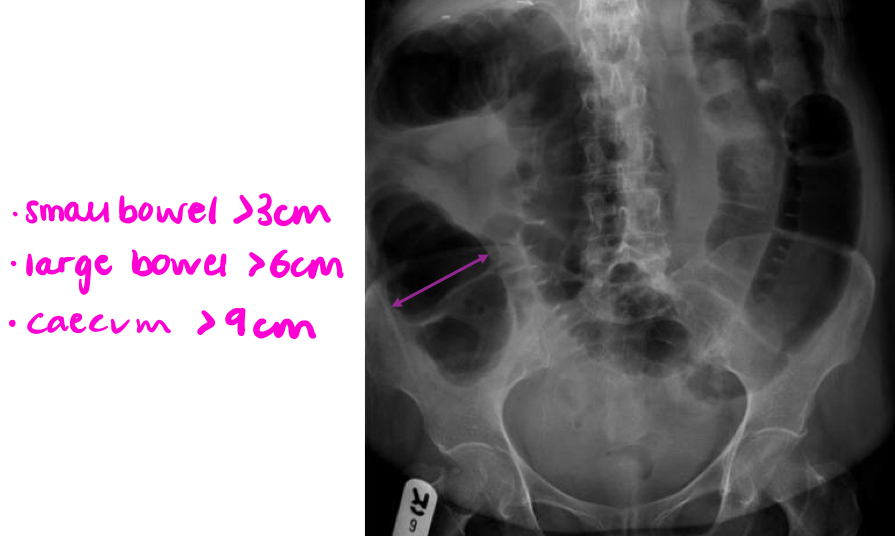

What symptoms can bowel obstruction cause and how can we diagnoses a bowel obstruction?

What are some differentials for bowel obstruction?